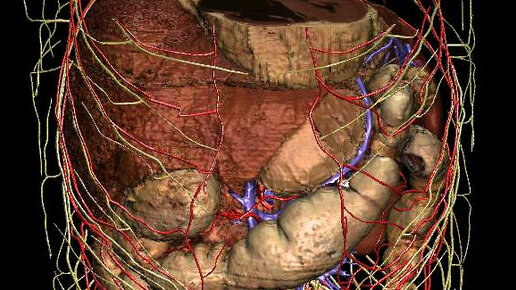

КТ брюшной полости является современным и точным рентгенологическим способом диагностики органов, расположенных в брюшной области. Во время обследования происходит томографическое, то есть, послойное сканирование исследуемой зоны. Современные мультспиральные томографы способны за один оборот сканера делать от 32 до 640 срезов, а мощный компьютер может создать трехмерные реконструкции всех анатомических структур области живота. Данные КТ снимков позволяют выявить воспалительные процессы и опухолевые изменения в костных и мягкотканных структурах...

КТ брюшной полости (Полное название мультиспиральная компьютерная томография брюшной полости) с контрастом применяют для обследования состояния органов, тканей и лимфатических узлов при подозрении на опухолевые или воспалительные заболевания...